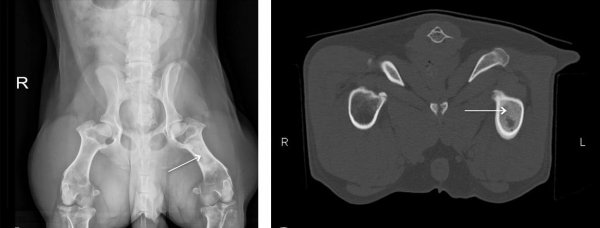

折耳猫天生就有遗传性骨骼疾病,这种病让它们的身体骨骼发育受到了严重的影响。